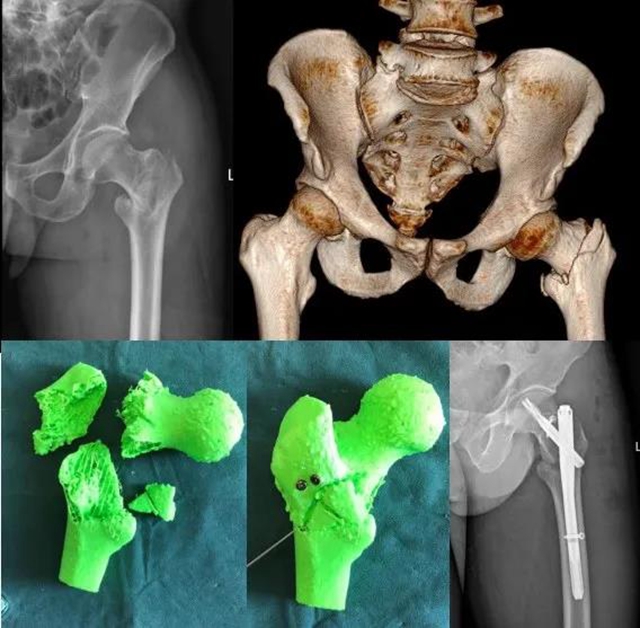

这些打印出来的骨骼模型将用于给骨盆粉碎性骨折的陈先生做术前模拟手术演示。

术前,刘宗超博士后手术团队,利用3D打印术,为陈先生做了手术规划,2021年8月28日,历时3小时,成功完成了“右侧骨盆髋臼粉碎性骨折+右侧桡骨远端粉碎性骨折切开复位内固定+左侧桡骨远端粉碎性骨折闭合复位外固定支架固定术”的多部位骨折手术。

1、借助3D打印技术,根据患者CT三维重建数据构建出1:1的3D模型,能准确了解骨折类型,为患者和医生提供触觉与视觉上的体验;

2、能提前预演术中步骤,在体外完成模拟手术,为患者量身定制最佳治疗方案,精准度高;

3、手术时间明显缩短,术后2-3天手术部位便能活动,并能进行早期功能锻炼,更利于功能康复。